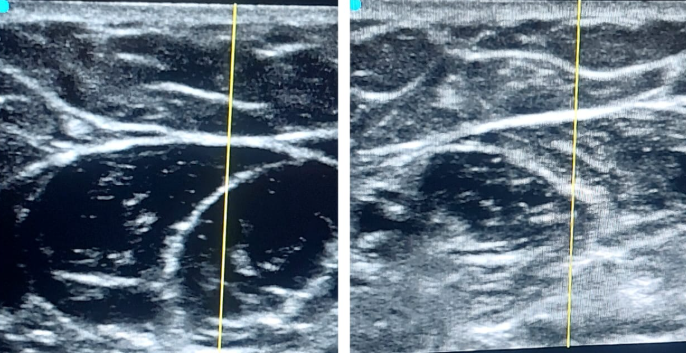

Dr. Abraham’s submission includes:

📷 An image taken during the stellate ganglion block procedure